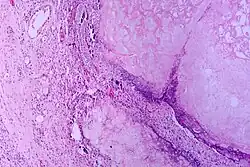

Pancreatic Ductal Adenocarcinoma (PDAC) is one of the most lethal cancers and has an expected survival of five years.[11] Pancreatic adenocarcinoma cells resemble pancreatic ductal cells. Both cell groups show tubule formation, cuboidal shape, and ductal markers. Additionally, acinar and endocrine cells have often been found in many of these cancers, demonstrating plasticity and the possibility that the initial target cells are pancreas progenitor cells.[3] Moreover, human tumors usually go with lower-grade lesions that are called pancreatic intraepithelial neoplasias (PanINs) and are in ducts. Because these lesions are in ducts, this means that it is possible that the beginning target cells are ductal cells.